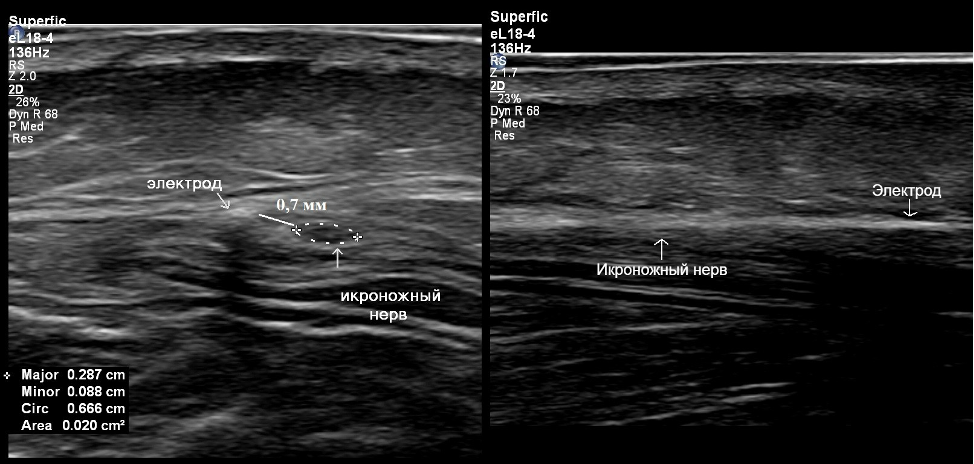

В 2023г. пациентка обратилась в ФГАУ «НМИЦ Нейрохирургии им.ак.Н.Н.Бурденко» Минздрава России. Ей было предложено выполнение блокады икроножного нерва, что и было выполнено. Отметился полный регресс болевого синдрома на время действия местного анестетика с полным рецидивом болевого синдрома на 2-3 день после блокады. В связи с этим пациентке было решено проведение имплантации электрода для хронической электростимуляции икроножного нерва под УЗИ-контролем. На задне-латеральной поверхности голени выполнен линейный разрез длиной 3 см, через который под ультразвуковым контролем идентифицирован ствол икроножного нерва. С использованием иглы Туи произведена имплантация электрода параллельно ходу икроножного нерва с последующей фиксацией в области разреза толстой нерассасывающейся шелковой нитью (5 metric). (рис.2,3).

Рисунок 3. УЗ-картина имплантированного электрода. Слева – поперечное сканирование: электрод и икроножный нерв подписаны. Видно, что электрод идёт вдоль ствола икроножного нерва на расстоянии от него менее 1 мм. Справа – продольное сканирование: вывести электрод и нерв в одну плоскость крайне затруднительно из-за их взаимного расположения, но можно визуализировать тень от электрода и эпиневрий икроножного нерва.